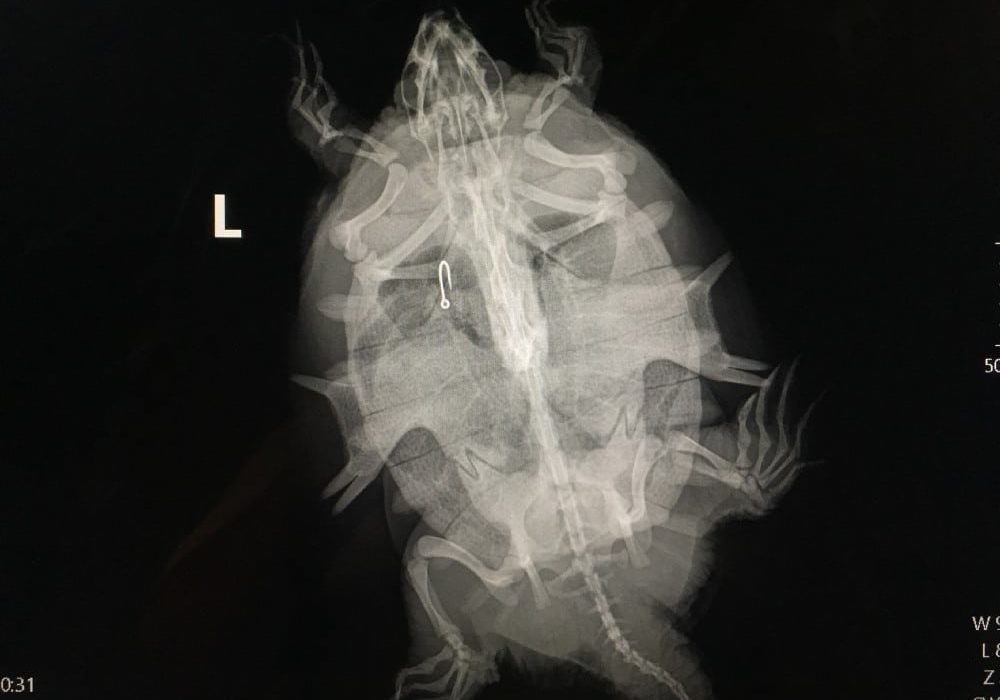

Several patients suffer from fishing hook injuries

A double crested cormorant and a Florida softshell turtle were among the 73 animals admitted to the von Arx Wildlife Hospital at the Conservancy of Southwest Florida this past week.…